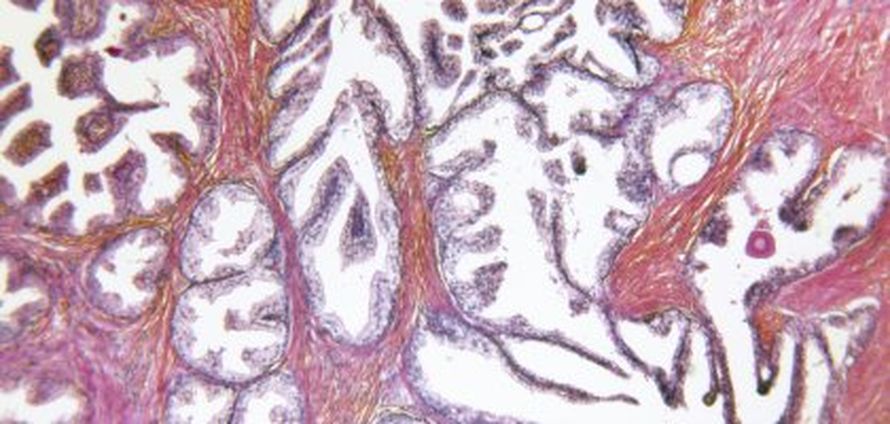

Seulonta perustui verestä määritettävään merkkiaineeseen, prostataspesifiseen antigeeniin eli PSA:han. Kuolleisuus aleni samassa suhteessa kuin vastaavissa rintasyövän ja suolistosyövän seulontaa koskevissa tutkimuksissa.